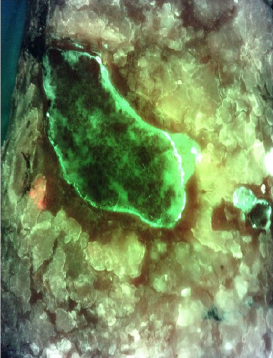

Detection of bacterial fluorescence from in vivo wound biofilms using a point-of-care fluorescence imaging device

Lopez, AJ et al. Int Wound J 2021